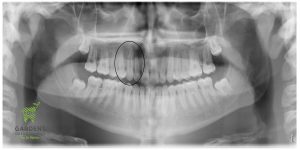

Initial and Final Panoramic X-rays showing an impacted canine (upper right) erupted in place